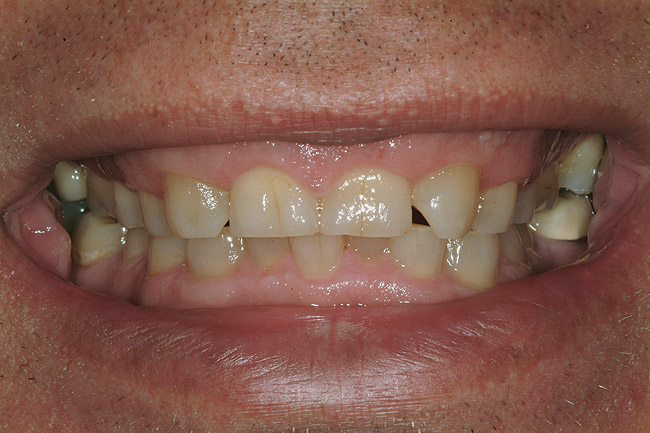

Un bărbat în vârstă de 48 ani, clinic sănătos, s-a prezentat pentru consultaţie, reclamând în principal zâmbetul său dezagreabil. Era îngrijorat cu privire la pierderea progresivă a structurii dentare pe care a constatat-o în decursul ultimilor ani şi cu privire la colorarea generalizată şi afişarea inadecvată a dinţilor şi gingiilor sale. Imaginile retractate preoperatorii relevau o formă de arcadă îngustă cu înghesuire minoră, uzură severă şi eroziune, alături de formarea unor torusuri voluminoase în regiunile maxilare vestibulare1 (fig. 1).